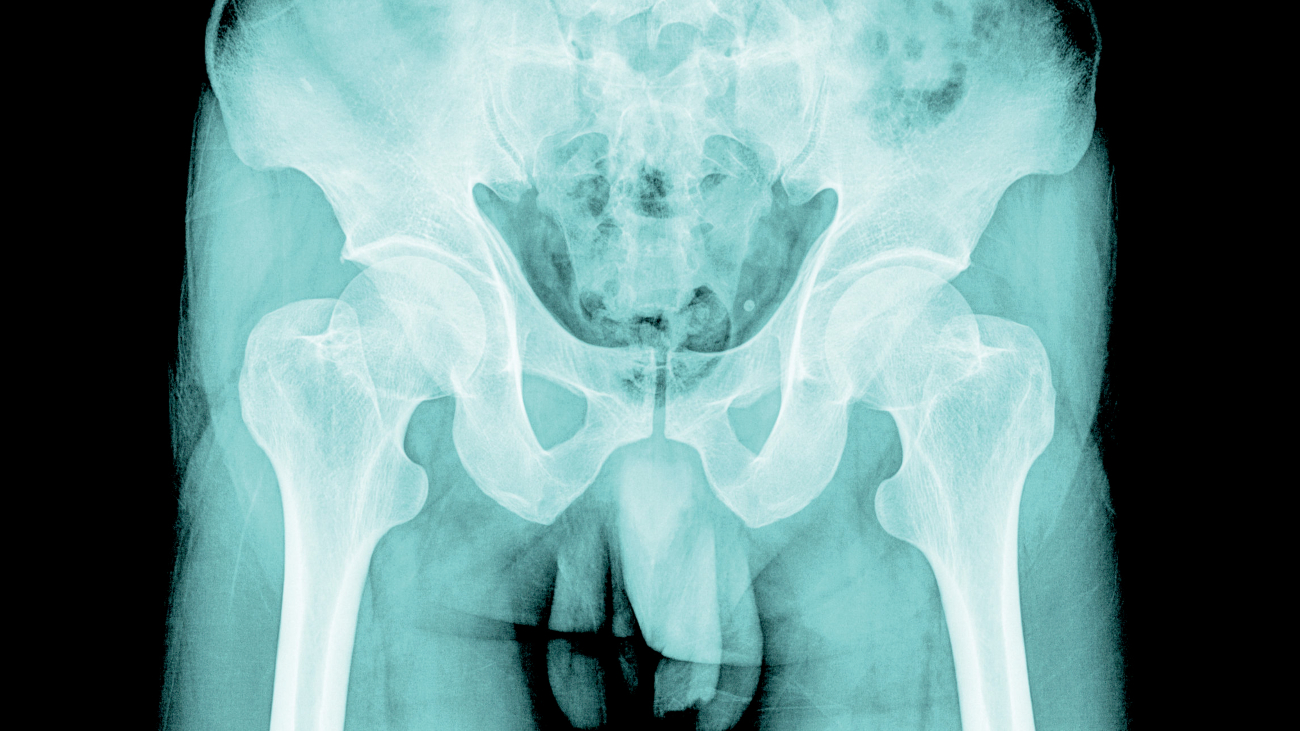

Al onze naaste verwanten, zoals de chimpansee en de gorilla, hebben er eentje: een botje in de penis om hem stijf te houden. Maar mannelijke mensen moeten dat voor elkaar krijgen met zwellichamen. Waarom?

En een penis met zwellichamen is bij uitstekgeschikt voor veelvuldige maar kortstondige seks. Andere primaten doen het alleen als het vrouwtje vruchtbaar is, maar dan voor lange tijd, zodat de concurrentie geen kans heeft. Voor zulke seks is een penis met een botje – die immers nooit verslapt – juist handig.

Theorie twee wil dat het functioneren van de zwellichamen het nodige zegt over de gezondheid van een man, wat het voor een vrouw makkelijker maakt om een fitte man uit te zoeken. Mannen met zowel lichamelijke en/of geestelijke problemen krijgen hem immers niet lekker snel omhoog.